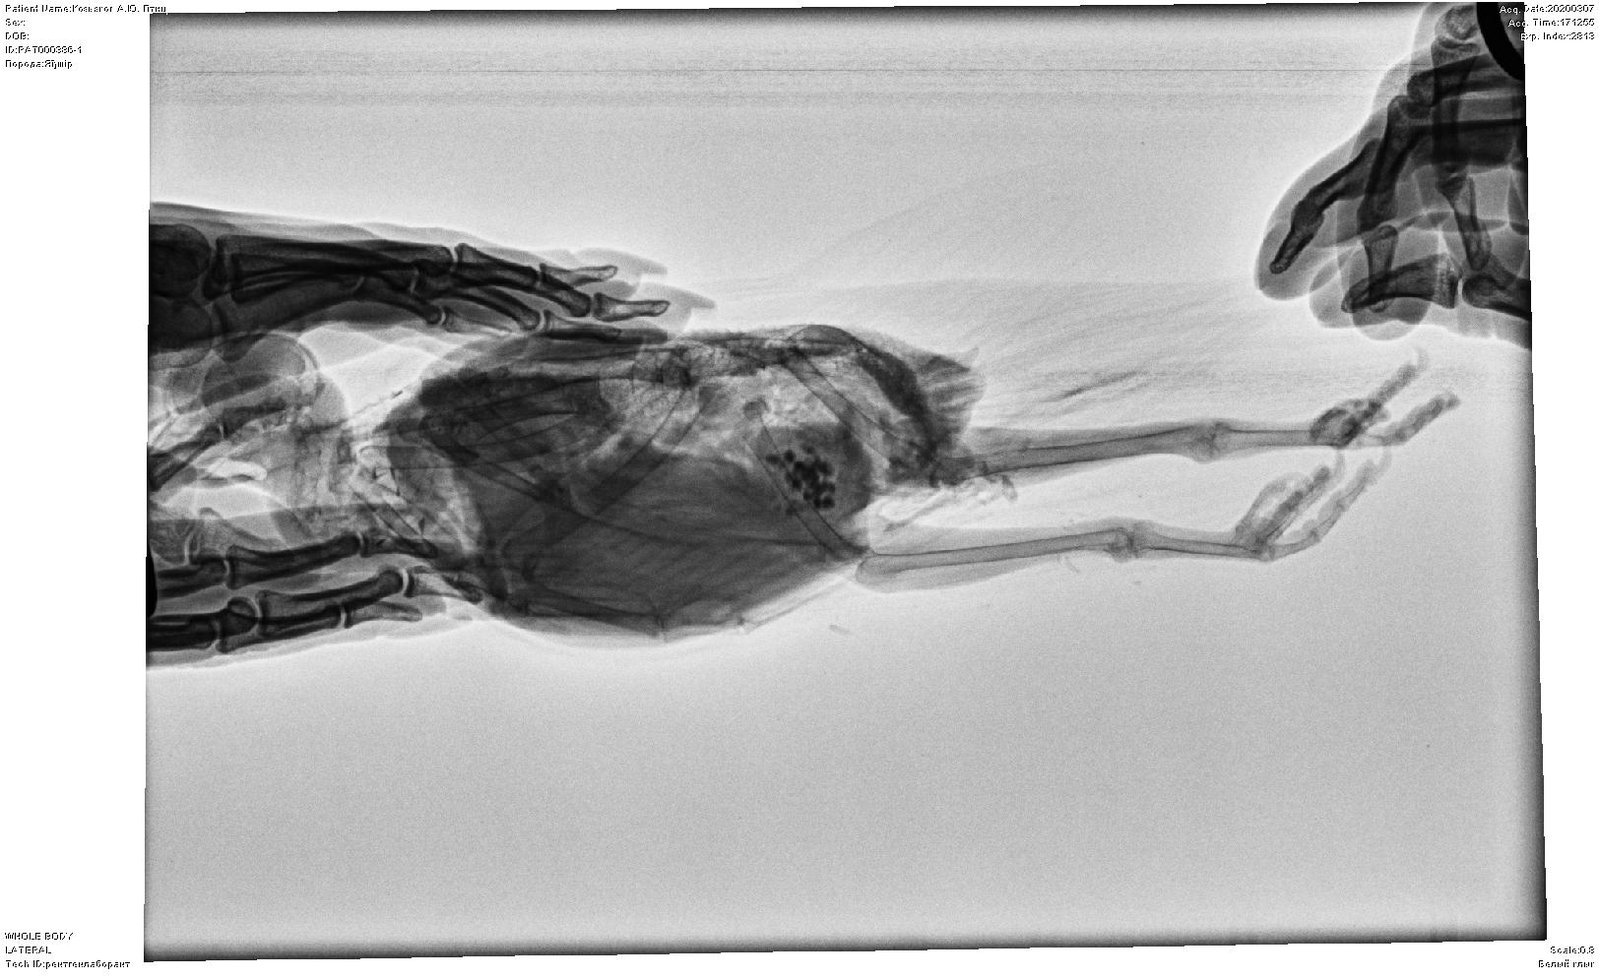

Elena1811 Опубликовано 7 марта, 2020 Автор #113 Опубликовано 7 марта, 2020 Мы старались как могли. Не получается его развернуть полностью из-за левого крыла. Не разворачивается доконца. Боялись сломать

Elena1811 Опубликовано 7 марта, 2020 Автор #115 Опубликовано 7 марта, 2020 5 минут назад, маленький принц сказал: позвал в тему Зосю Спасибо. Будем ждать. И надеюсь снимки читабельны

Elena1811 Опубликовано 7 марта, 2020 Автор #116 Опубликовано 7 марта, 2020 Нам их дополнительно скинули на флэшку

Zosia Опубликовано 7 марта, 2020 #124 Опубликовано 7 марта, 2020 Если есть файлы на флешке- то мне на почту киньте. Т.к. в переснятом виде снимки нечитабельны. zofia68@mail.ru

Elena1811 Опубликовано 11 марта, 2020 Автор #130 Опубликовано 11 марта, 2020 Получила ответ от Зофии. Нужны разъяснения. И некоторые препараты я не могу купить Вот что пишет Зофия: Ну, отличить голубя от голубки я по фото не смогу. Хотя ИМЪО мне видится голубка. И те новообразования в брюшной полости (которые могцт передавливать нервные окончания, идущие к лапкам)- характерны именно для голубок, у меня даже фото есть гранулем, которые у них «рождаются» вместо яиц. Так что ИМХО- итраконазол в дозе 15 мг/кг каждые 12 чсов, нисиатин в дозе 75 000 ед в сутки на 100 гр веса, преднизолон из арсчета 3 мг/кг в сутки. Первый курс- 21 день. Для прикрытия преднизолона- Деринат капли назальные, принимать орально 4 капли в сутки весь курс. Обязательно гепатовте- 0,2-0,3 мл в сутки. По крылу- ваш снимок не дает возможности оценить фатальность нарушений. Но скорее всего- там уже вряд ли что можно сделать (и по-любому это вопрос-не вопрос жизни). ......... У нас беда с преобретением лекарств, рецепты только лишь на аналгин не нужны..